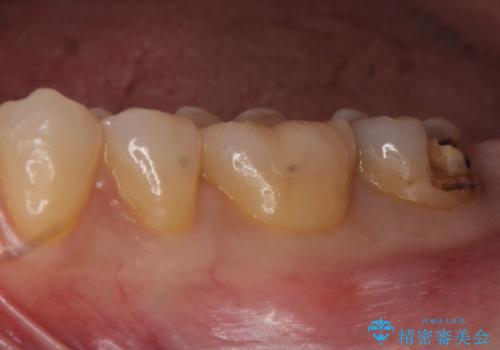

- 銀の詰め物が取れたとのことで来院。

詰め物の下には虫歯がありました。

白い物で治療して欲しいとのことで、セラミックの詰め物だと詰め物の範囲が大きく、割れてしまう可能性があるので

ジルコニアクラウン(被せもの)で治療を行いました。

銀の詰め物はかなり昔に治療されたそうです。

銀の詰め物は虫歯の再発リスクが高く、歯に痛みが出てしまうと歯の神経の治療もしないとならなくなってしまいます。